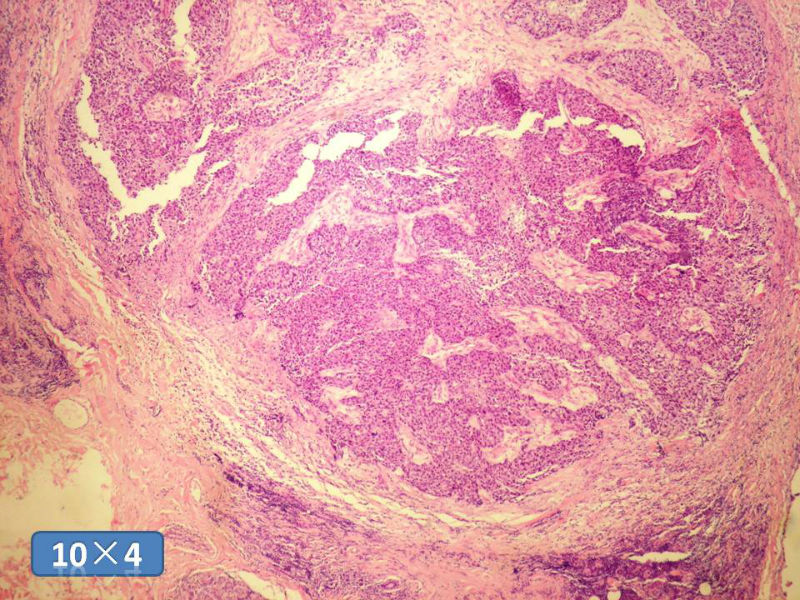

女性,50岁,乳腺肿物,冰冻切片(图1-25)

图1

HE